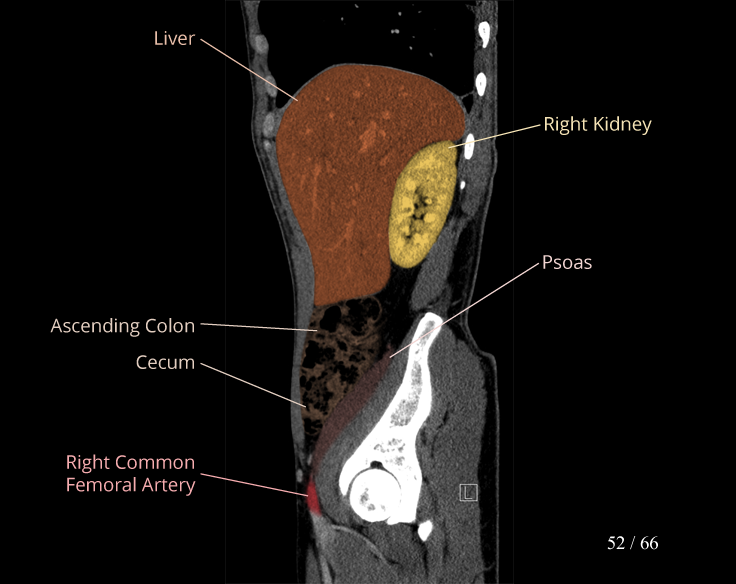

Body

Covers abdominal CT anatomy.